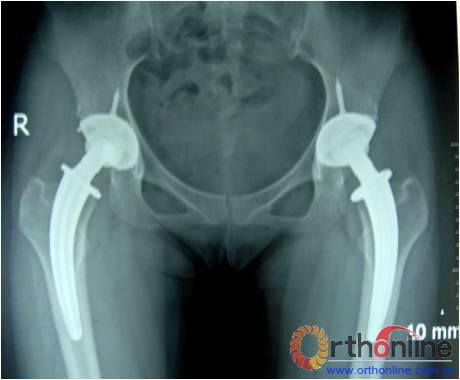

图为:方某,女,21岁,双侧激素性股骨头坏死,ARCO III-C期,C.F.P. 股骨假体THA前后双髋X线摄片。

图1、图2:术前;图3:术后;图4:术后3个月;图5:术后6个月;图6:术后1.2年

本组随访时间:12~30个月,平均18.1个月。平均切口长度9.5cm(8~12)cm。术中出血量平均400 ml(250~800ml),输血量平均320 ml(0~800ml),引流量平均350 ml(200~800ml)。95%患者于术后第1天可持拐活动、小距离行走,关节功能恢复均较理想。平均术后6周(3~8)周弃拐行走。按照Harris评分标准,术前平均为(42.8±8.6)分(21~52分),终末随访时提高到平均(92.8±6.1)分(80~100分),优7髋,良2髋。X线片上股骨假体与股骨髓腔匹配良好,髋臼和股骨无骨吸收或骨溶解,假体无松动征象,稳定性良好。疼痛解除,双下肢等长,无跛行。

本组病例术后无感染、下肢深静脉血栓、关节脱位、异位骨化、大腿痛、假体松动下沉等并发症发生。平均随访18.1个月,优7髋,良2髋。X线片上股骨假体与远端股骨髓腔匹配良好,假体周围骨无骨吸收与溶解,假体在位率高。而且,疼痛解除,无跛行,效果令人满意。